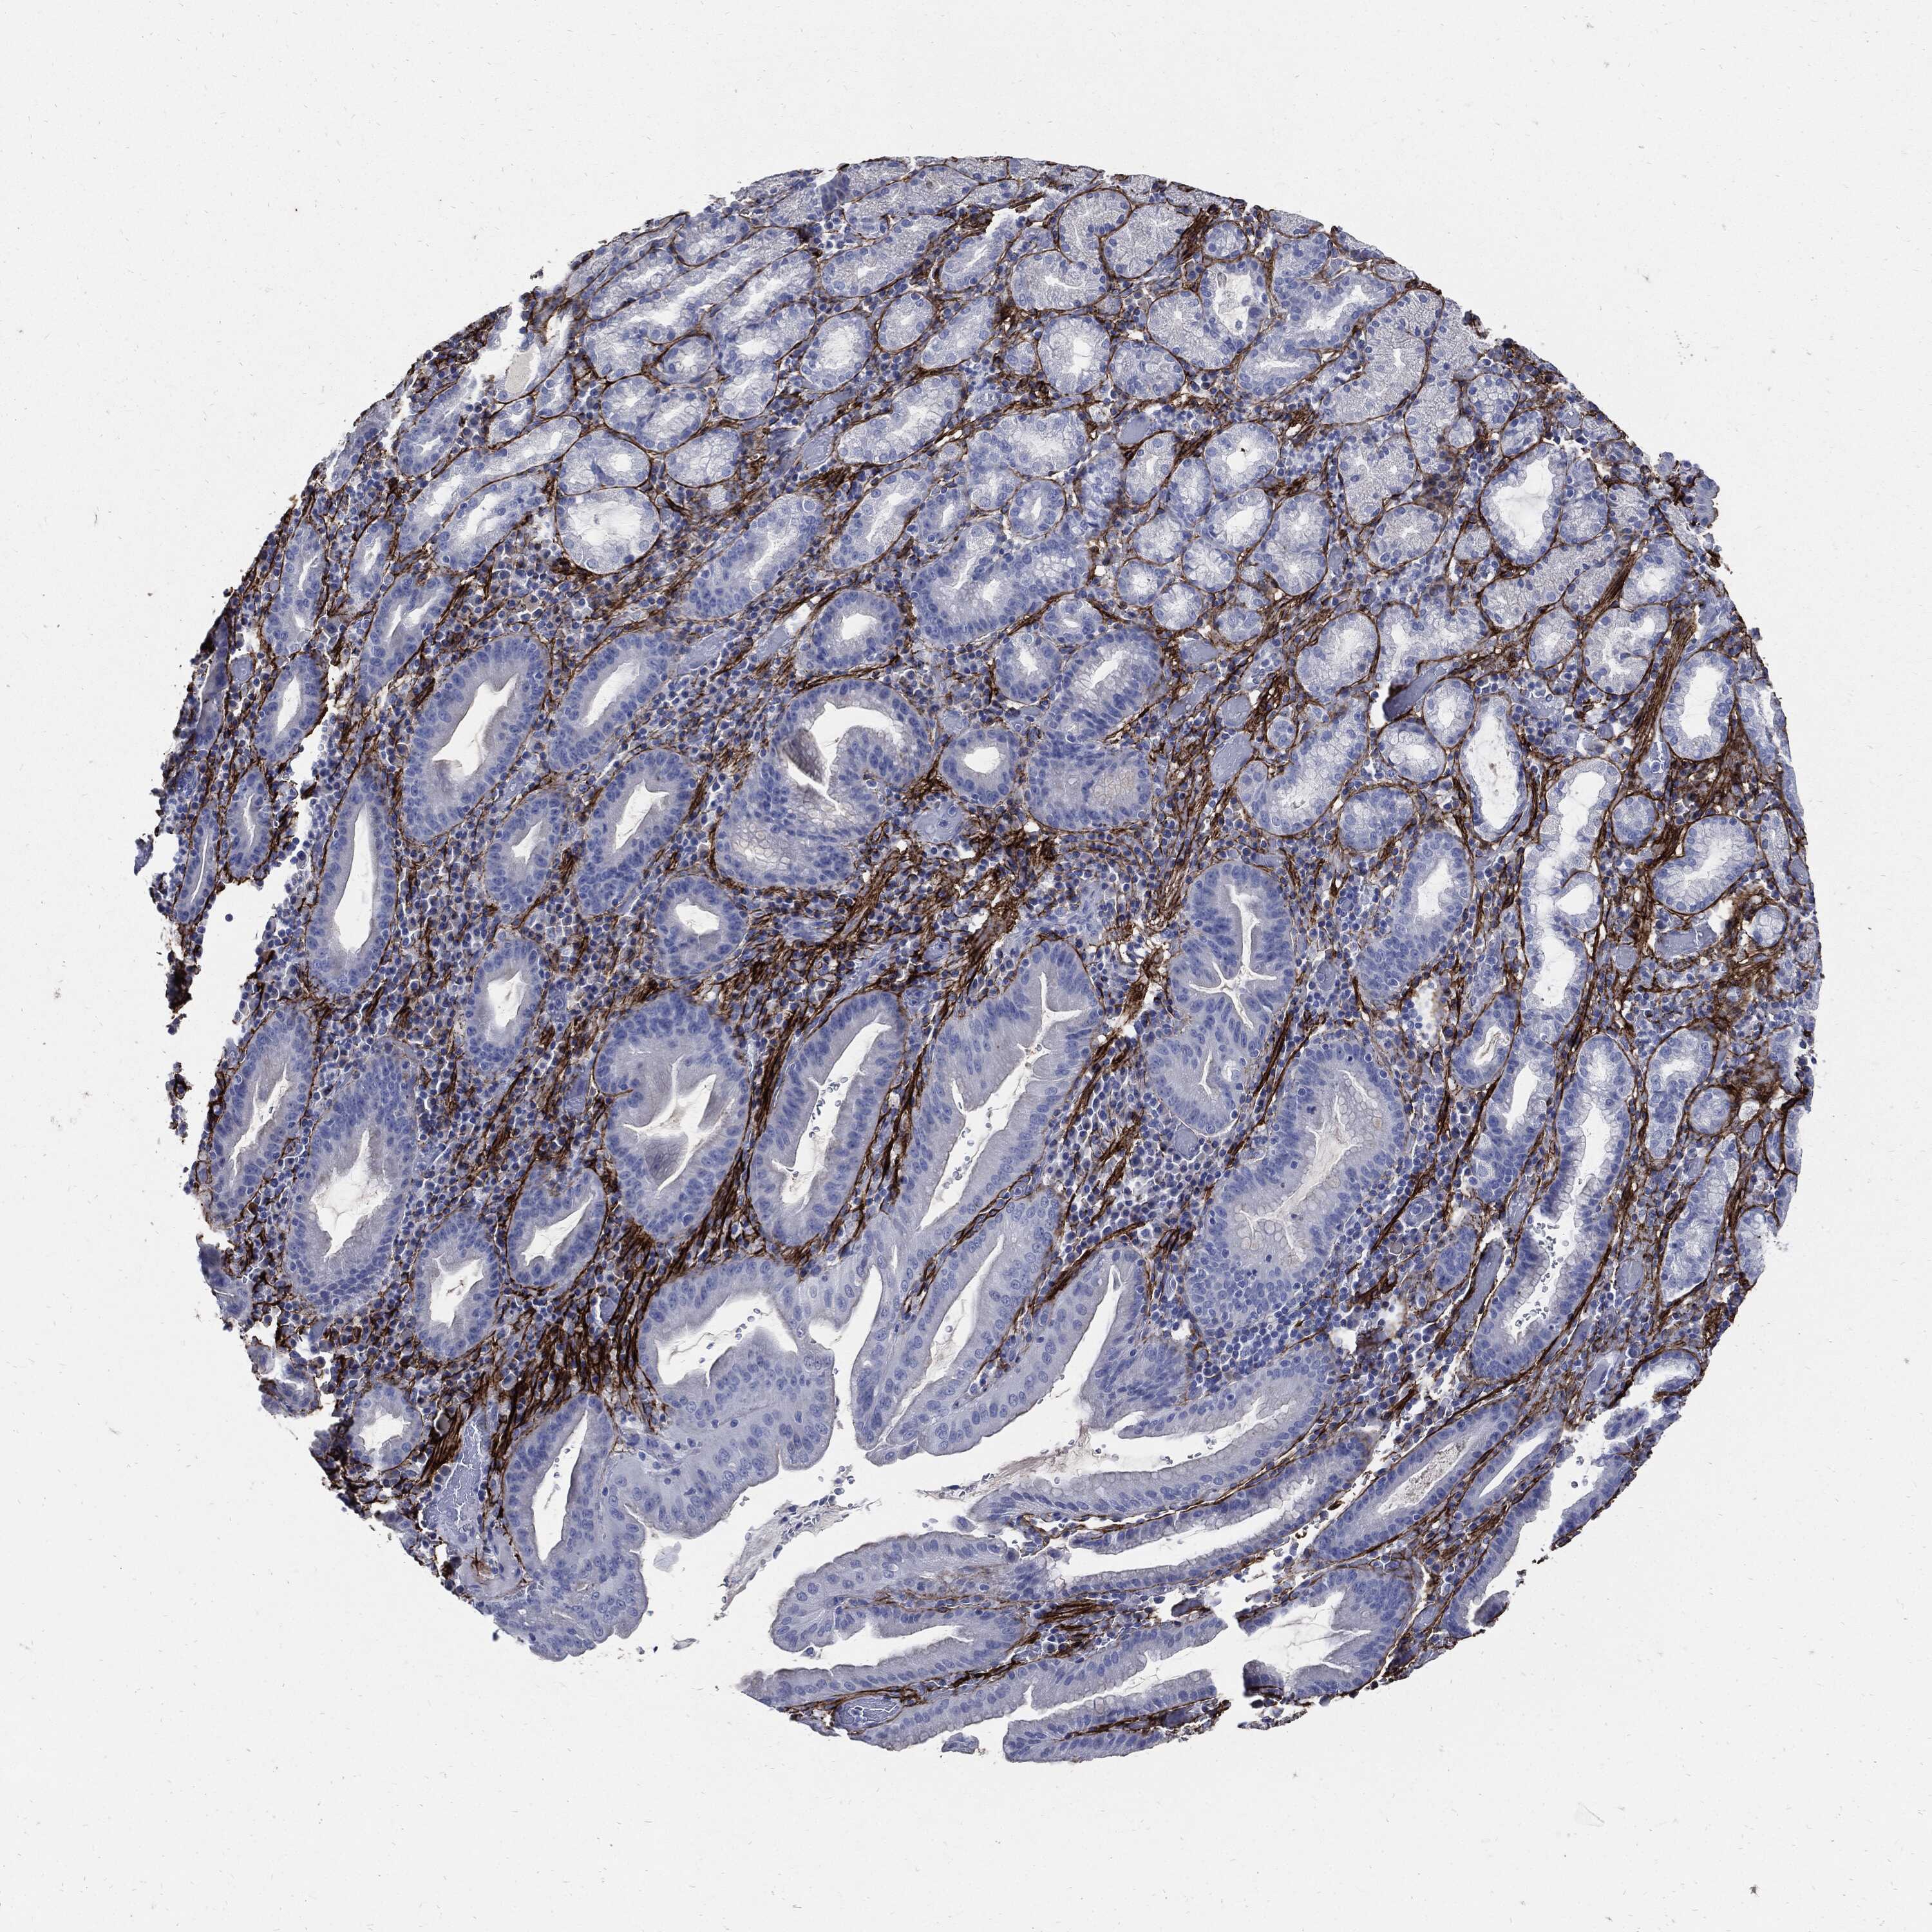

STOMACH CANCER - Protein expressioni

A mouse-over function shows sample information and annotation data. Click on an image to view it in a full screen mode. Samples can be filtered based on level of antibody staining by selecting one or several of the following categories: high, medium, low and not detected. The assay and annotation is described here.

Note that samples used for immunohistochemistry by the Human Protein Atlas do not correspond to samples in the TCGA dataset.

Antibody stainingi

Antibody staining in the annotated cell types in the current human tissue is reported as not detected, low, medium, or high, based on conventional immunohistochemistry profiling in selected tissues. This score is based on the combination of the staining intensity and fraction of stained cells.

Each image is clickable and will lead to virtual microscopy that enables deeper exploration of all samples and also displays staining intensity scores, fraction scores and subcellular localization as well as patient and tissue information for each sample.

HPA017759

HPA021057

CAB002670

CAB058696

CAB068188

CAB080202

Staining

High

Medium

Low

Not detected

Intensity

Strong

Moderate

Weak

Negative

Quantity

>75%

75%-25%

<25%

None

Location

Nuclear

Cytoplasmic/membranous

Cytoplasmic/membranous,nuclear

Adenocarcinoma, NOS

Adenocarcinoma, High grade